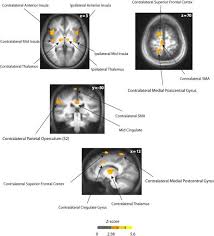

The Role Of Circulating Sex Hormones In Menstrual Cycle Dependent Modulation Of Pain Related Brain Activation Abstract Europe Pmc